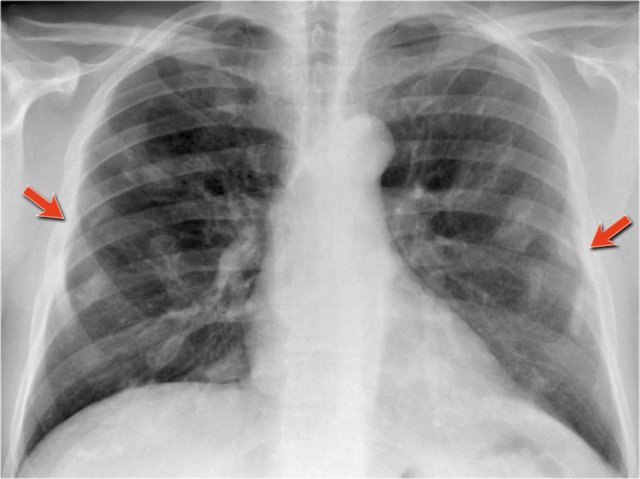

Once you compare the chest film to the old one, things become more obvious and you will be much more confident in your diagnosis of congestive heart failure:

- The size of the heart is slightly increased compared to the old film, but was already large on the old film.

- The pulmonary vessels are slightly increased in diameter indicating increased pulmonary pressure.

- There are maybe some subtle interstitial markings as a result of interstitial edema.

- There is pleural fluid bilaterally. Notice that the infero-posterior border of the lower lobes has changed in position.